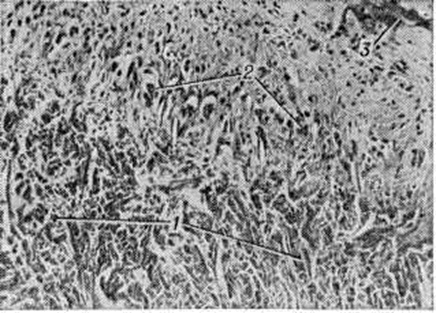

В гистологический картине синовита выделяют следующие изменения: 1) поражение сосудов микроциркуляторного русла; 2) гиперплазию и гипертрофию синовиальных клеток; 3) воспалительную клеточную инфильтрацию; 4) разрастание грануляционной ткани, склероз, липоматоз синовиальной собственной пластинки. Повышается проницаемость стенок сосудов микроциркуляторного русла, сопровождающаяся выходом фибринозного экссудата и образованием очагов фибриноида в синовиальной собственной пластинке и фибриноподобных наложений на поверхности синовиальной оболочки. Иммуноморфологически в очагах фибриноида и в фибриноподобных наложениях выявляются фибрин, иммуноглобулины (G, А, М) и С3-фракция комплемента. При обострении воспаления постоянно отмечается продуктивный или продуктивно-деструктивный васкулит с фиксацией в сосудистой стенке иммуноглобулинов и комплемента. В глубоких слоях синовиальной оболочки (смотри полный свод знаний) изредка определяются ревматоидные узелки — небольшие участки фибриноидного некроза, окружённые макрофагами и лимфоцитами. В 80% случаев встречается гиперплазия и гипертрофия синовиоцитов с характерным палисадообразным их расположением (рисунок 2). С помощью электронно-микроскопического исследования обнаружено, что гипертрофия синовиоцитов происходит за счёт гиперплазии их органелл, особенно зернистой эндоплазматической сети, полисом, аппарата Гольджи и лизосом (рисунок 3). В гиперплазии ворсинчатого слоя синовиальной оболочки участвуют синовиоциты всех трёх типов (А, В и С). На ранних стадиях обострения воспаления клеточная инфильтрация в синовиальной оболочке скудная, представлена лимфоцитами, макрофагами и полиморфно-ядерными лейкоцитами. В дальнейшем отмечается лимфоидно-плазмоцитарная инфильтрация (рисунок 4), иногда с формированием лимфоидных фолликулов. Параллельно при иммунофлюоресцентном изучении Т и В-лимфоцитов синовиальной оболочки при Ревматоидный артрит Банкхерст (A. D. Bankhurst) с соавторами (1976) выявил преобладание Т-лимфоцитов. В синовиальной оболочке отмечается значительная пролиферация фибробластов. В синовиальной собственной пластинке и фиброзном слое наблюдается разрастание грануляционной ткани с исходом в склероз (смотри полный свод знаний) и липоматоз (смотри полный свод знаний).

В патологический процесс при Ревматоидный артрит могут вовлекаться практически все внутренние органы. Наиболее часто поражаются почки, в которых выявляется амилоидоз (смотри полный свод знаний), реже гломерулонефрит (смотри полный свод знаний) и пиелонефрит (смотри полный свод знаний). Иногда наблюдается амилоидоз печени, желудочно-кишечные тракта, сердца, селезёнки. Поражение сердца и лёгких наиболее часто связано с полисерозитом (смотри полный свод знаний) или его последствиями в виде фиброзных спаек в полостях. В некоторых случаях обнаруживается клапанный эндокардит (смотри полный свод знаний) с формированием порока сердца, миокардит (смотри полный свод знаний) и кардиосклероз (смотри полный свод знаний), коронарит (смотри полный свод знаний) и коронаросклероз, хроническая пневмония (смотри полный свод знаний) и пневмосклероз (смотри полный свод знаний), обусловленные основным патологический процессом. В сердце и лёгких могут встречаться ревматоидные узелки. Изменения в центральная нервная система, как и в других органах, связаны с васкулитом, сопровождающимся гибелью нервных клеток, демиелинизацией и глыбчатым распадом осевых цилиндров аксонов. В скелетных мышцах при высокой общей активности заболевания отмечается картина локального миозита (смотри полный свод знаний). В единичных случаях в подкожной клетчатке выявляются ревматоидные узлы, которые на разрезе имеют вид крошащихся серо-жёлтых масс, окружённых фиброзной капсулой. При микроскопическом исследовании в них определяются бесструктурные некротические массы, к которым примыкает вал из палисадообразно расположенных гистиоцитов (рисунок 5).